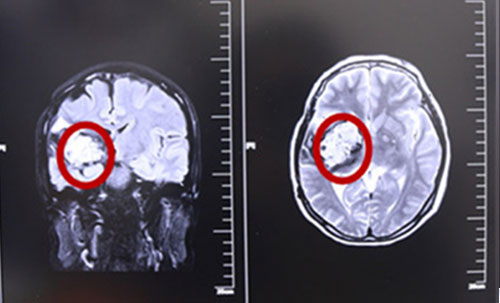

术前MRI影像资料,红圈内白色部分为肿瘤物

据核磁共振影像图示,患者脑内肿物靠近侧裂动脉,并向大脑深部丘脑生长,且位于运动区,已开始压迫脑干。我院多位专家,包括政府特殊津贴专家侯增欣主任等为制定详细的治疗方案,展开了会诊讨论,鉴于患者张XX发作性面部抽搐、肢体无力伴头晕等症状明显,结合MRI影像资料,一致认为颞顶海绵状血管瘤诊断明确,有手术指征。